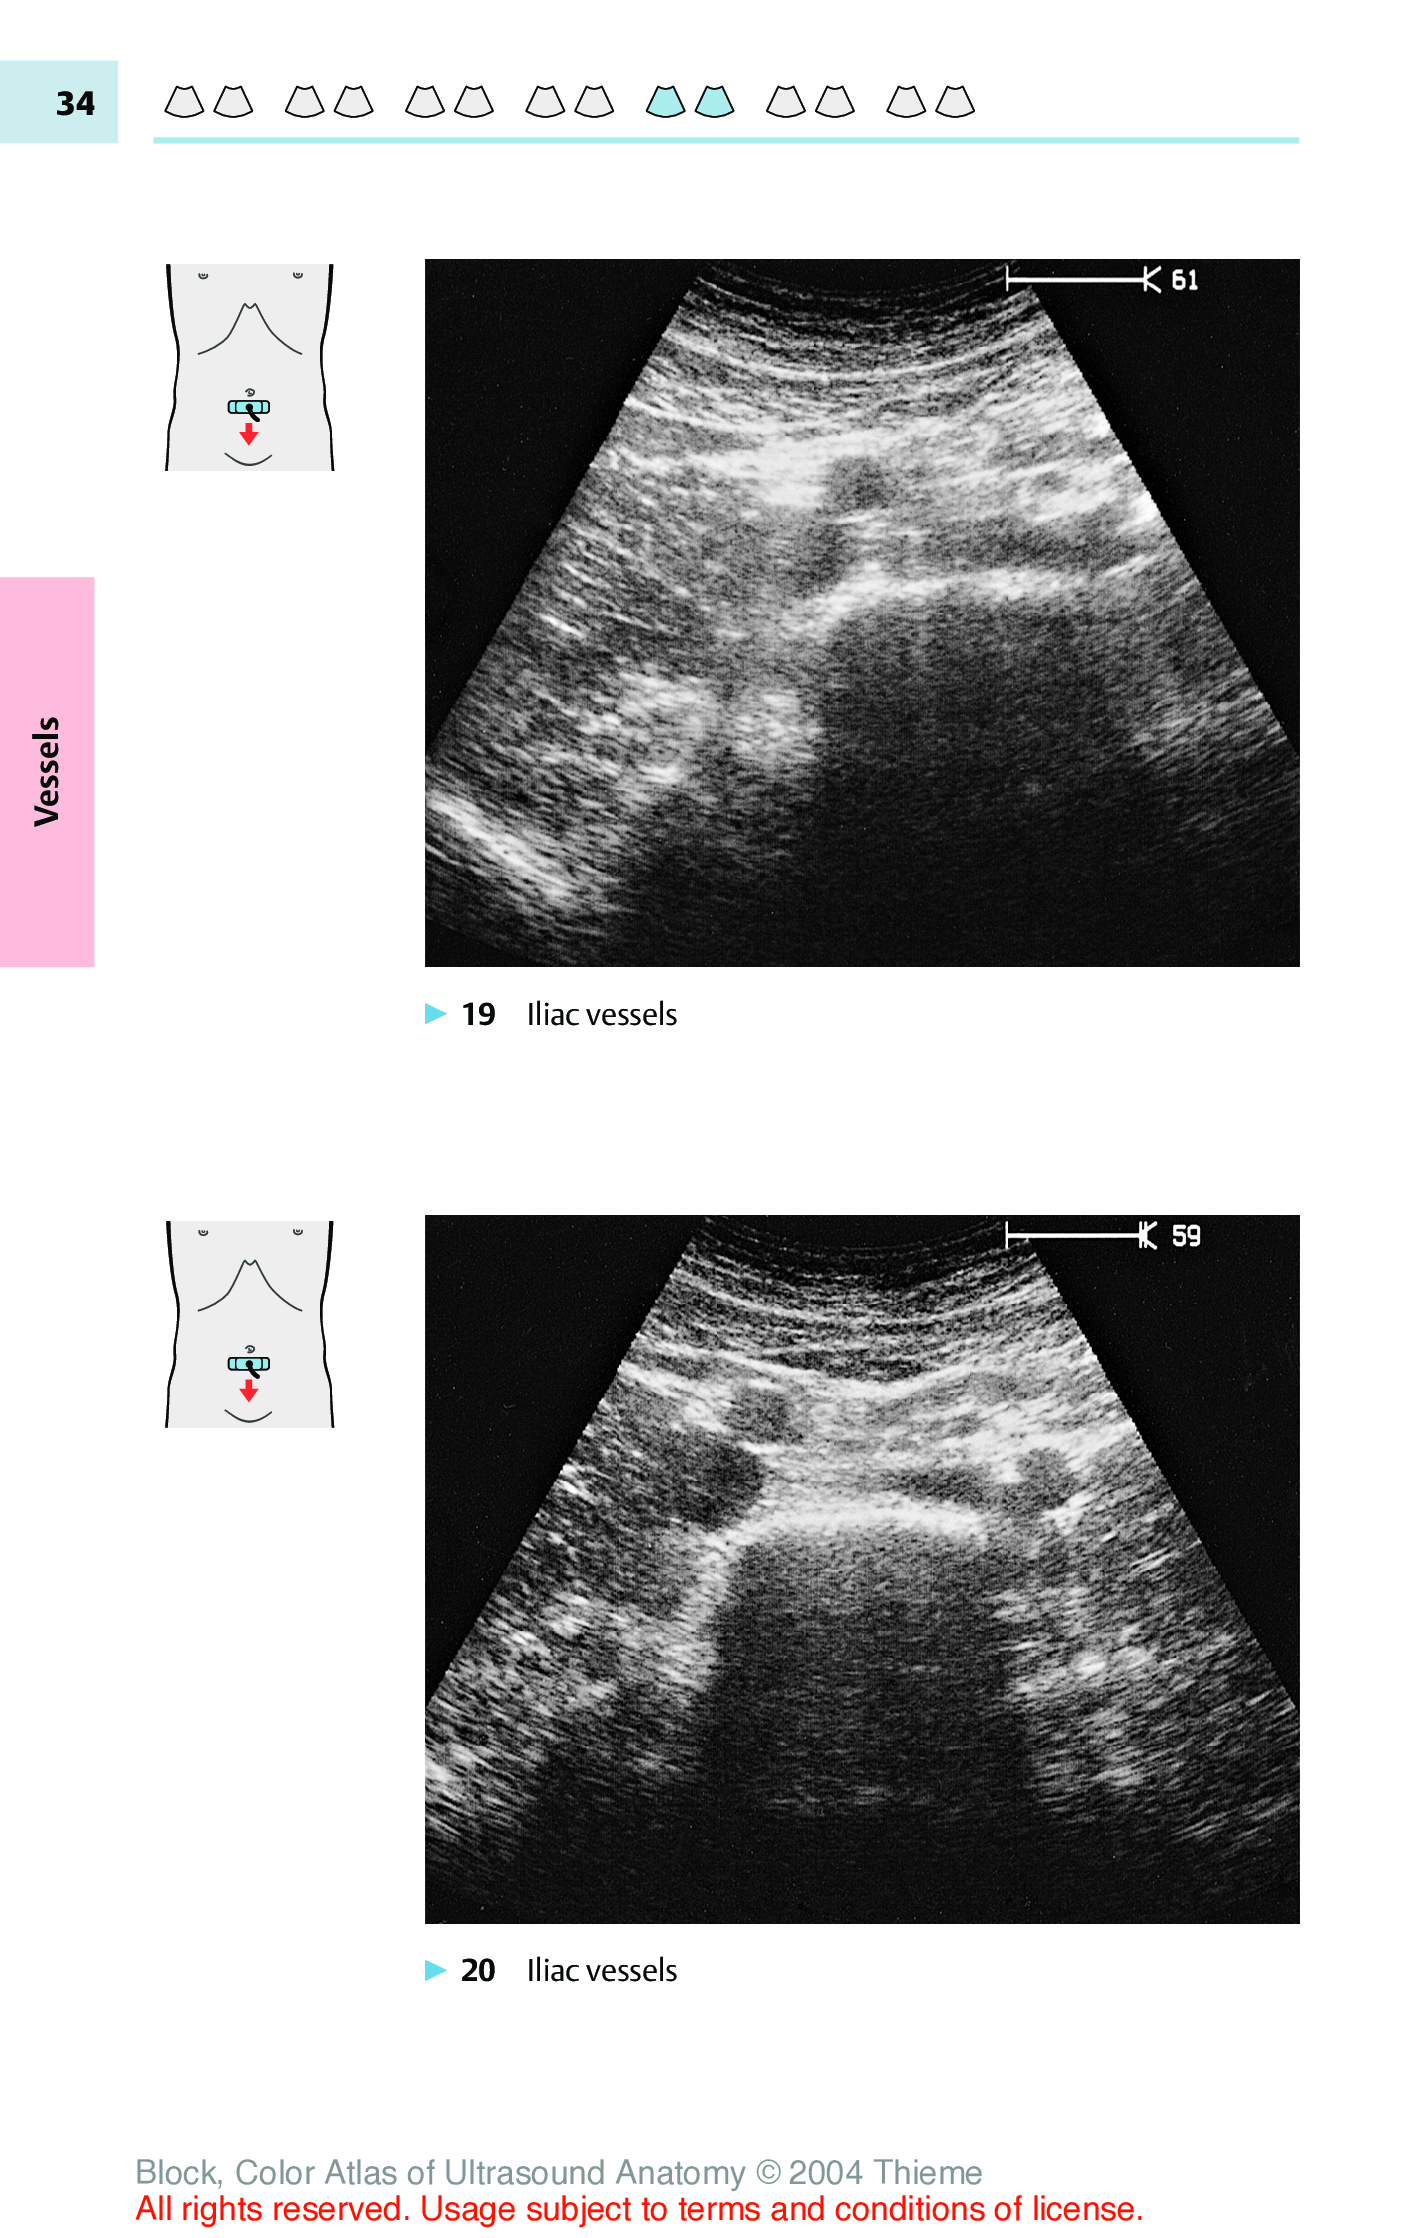

"Color Atlas Of Ultrasound Anatomy" - читать интересную книгу автора (Berthold Block)